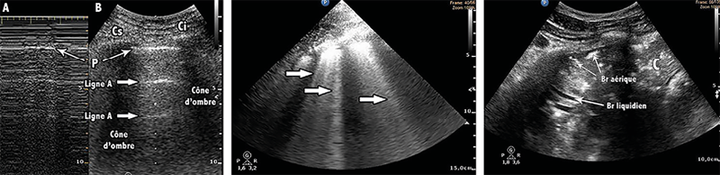

Cardio-respiratoire Monitoring de l'amélioration de l'aération pulmonaire par échographie après kinésithérapie respiratoire chez des patients sous ventilation mécanique